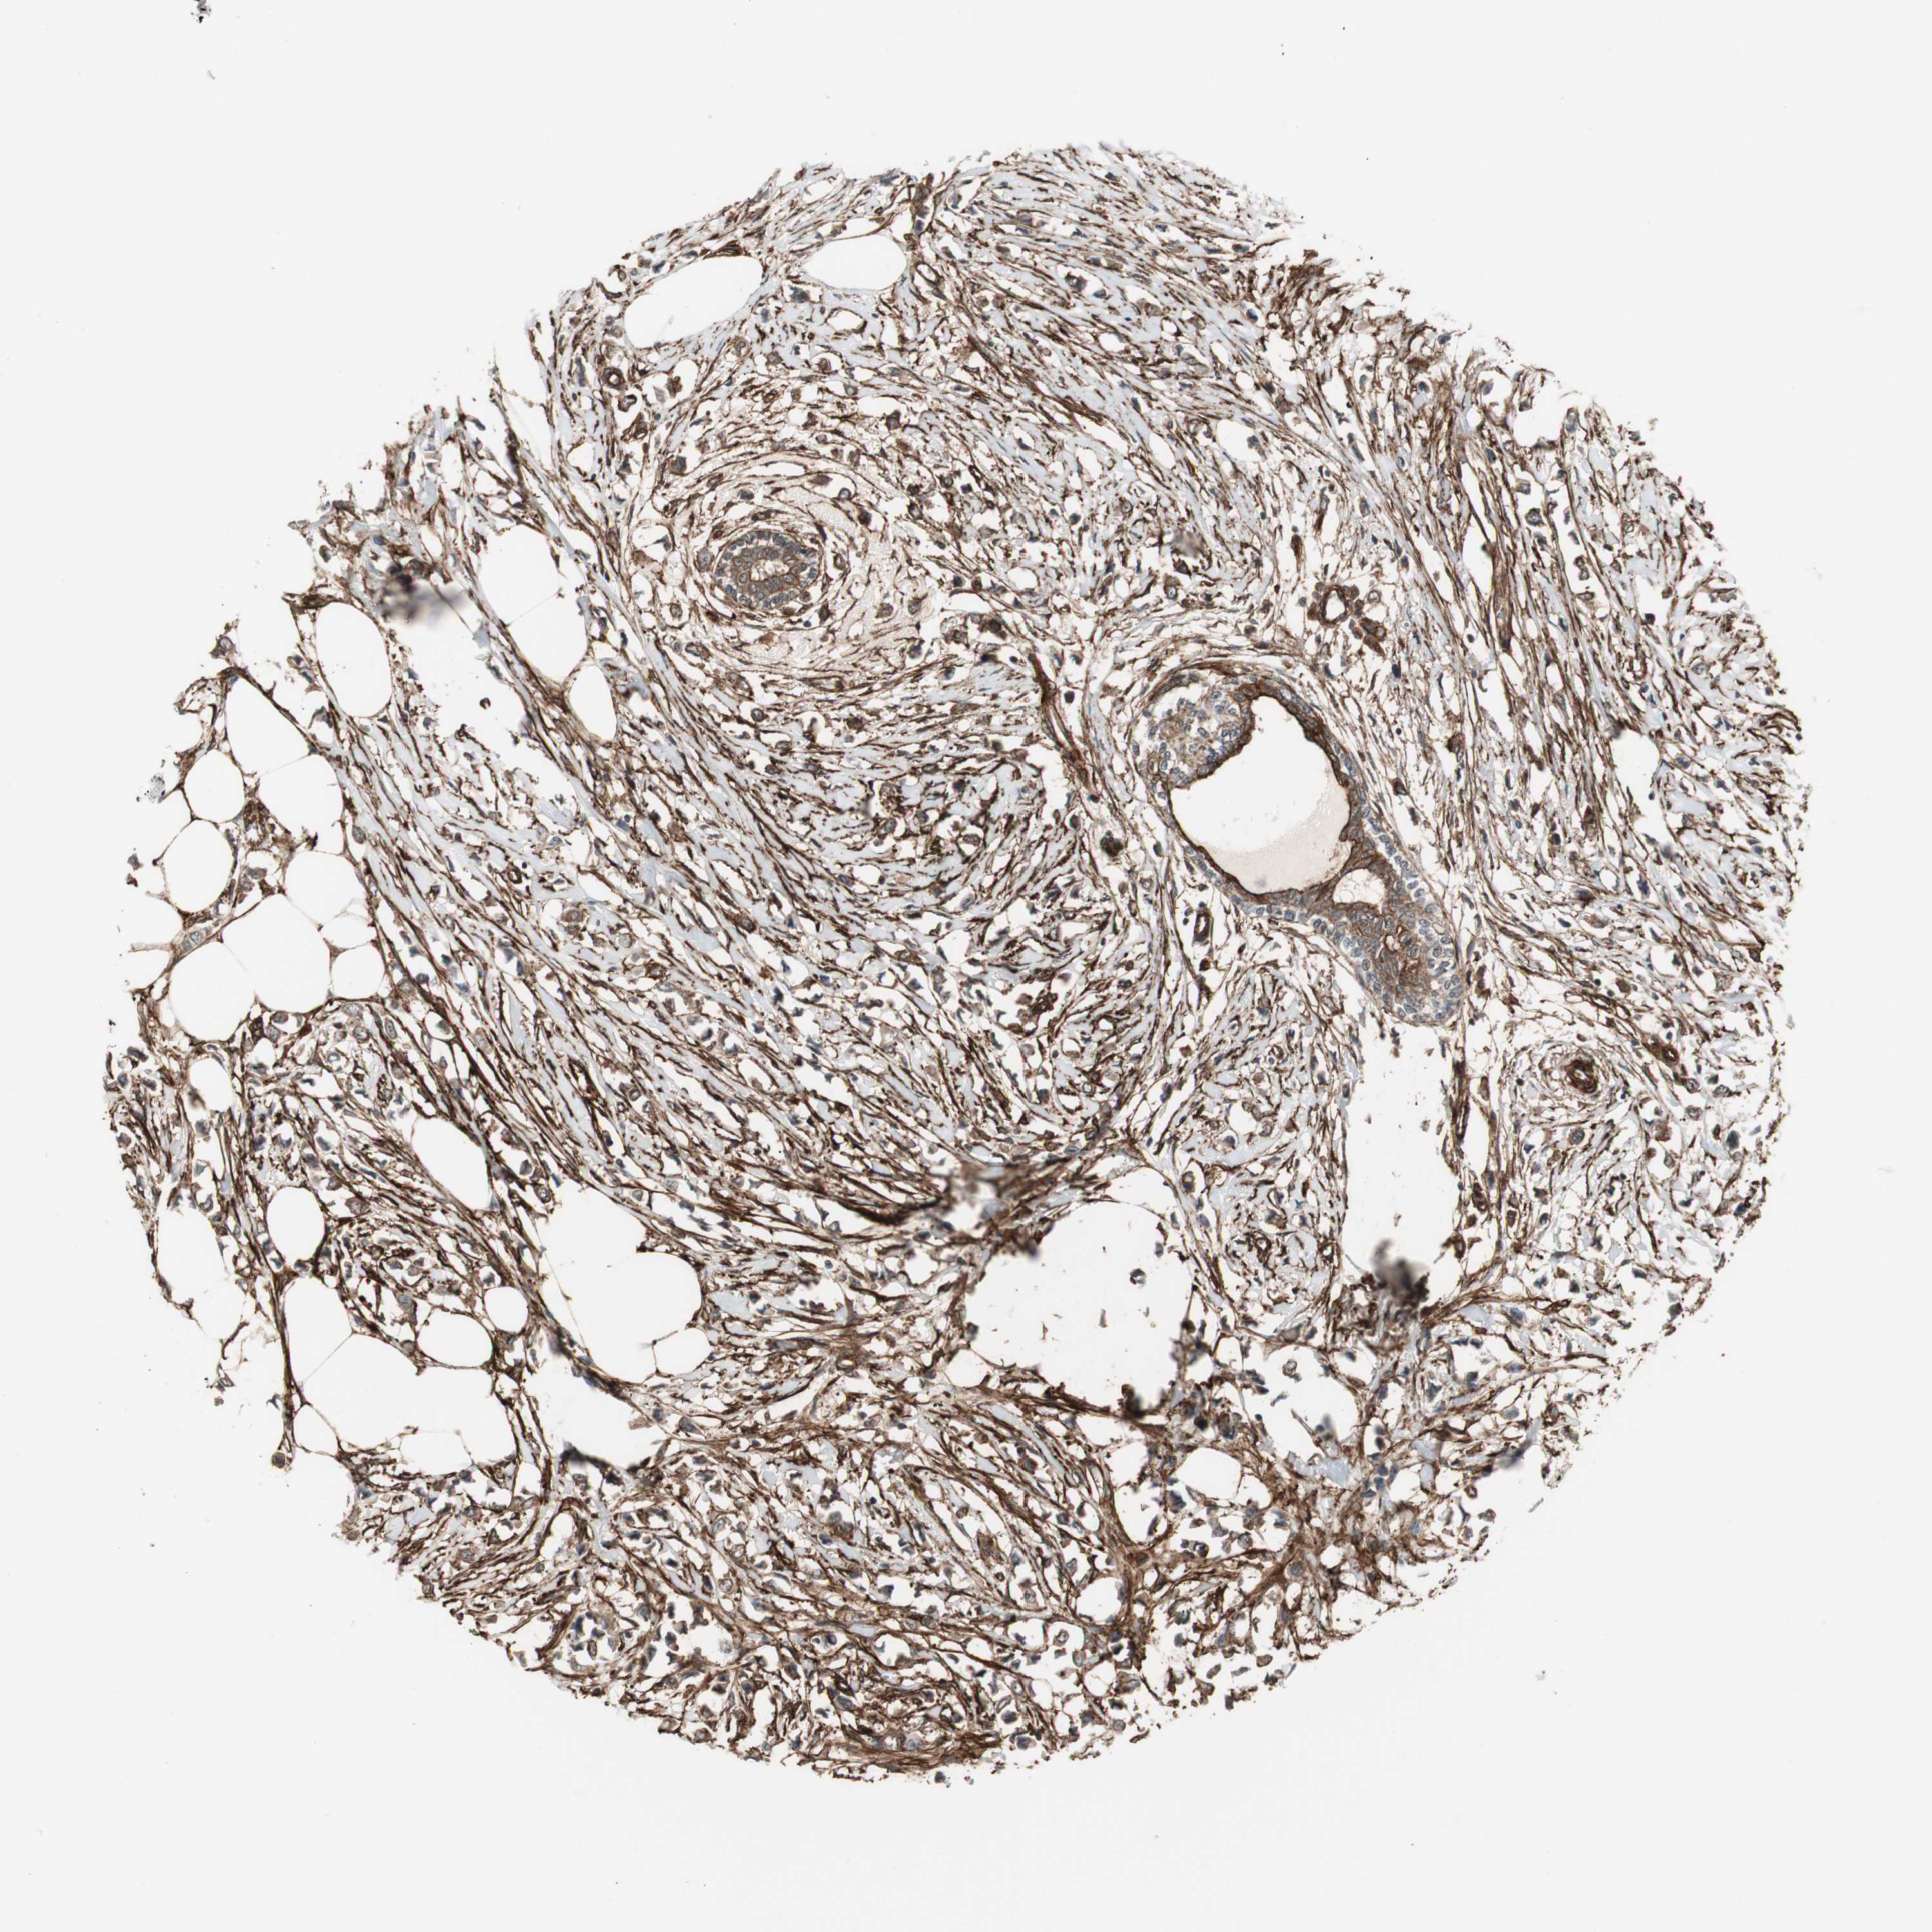

BRCA TCGA BRCA VALIDATION PROTEIN EXPRESSION

ANTIBODIES

AND

VALIDATION